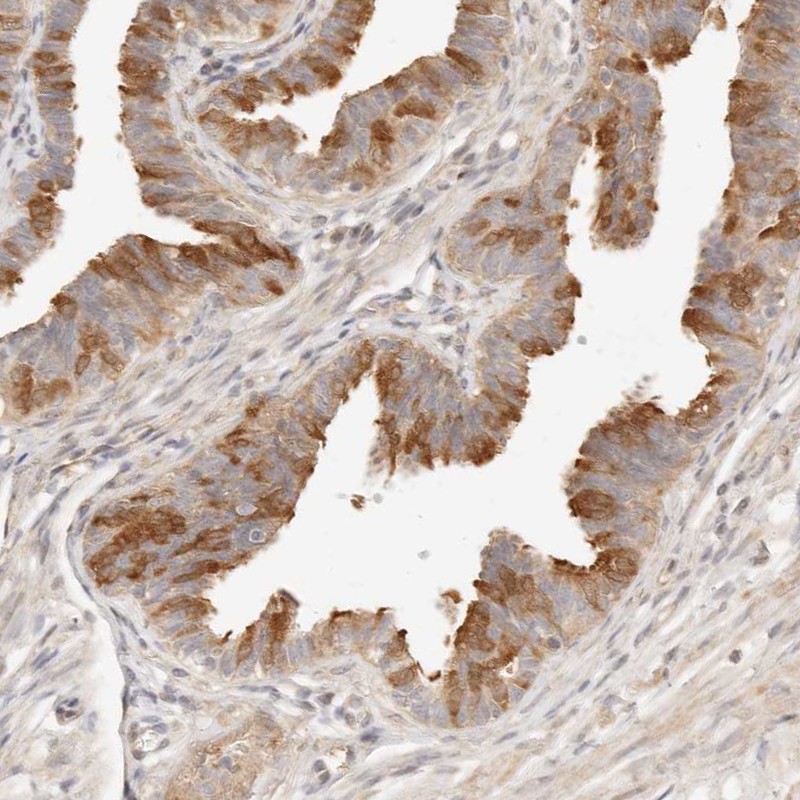

Immunohistochemical staining of human fallopian tube shows cytoplasmic positivity in glandular cells.